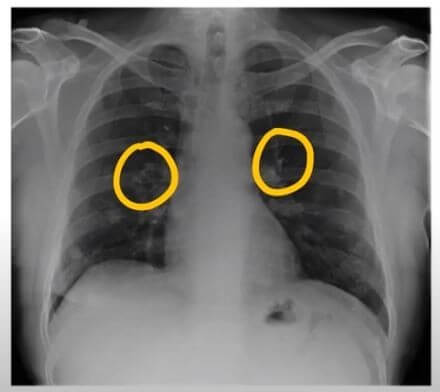

폐렴 원인

1) 세균

세균성 폐렴은 가장 흔한 유형의 폐렴입니다. 세균은 흡입되거나 혈류를 통해 폐에 들어갈 수 있습니다. 세균성 폐렴의 증상은 발열, 기침, 호흡 곤란, 가슴 통증입니다.